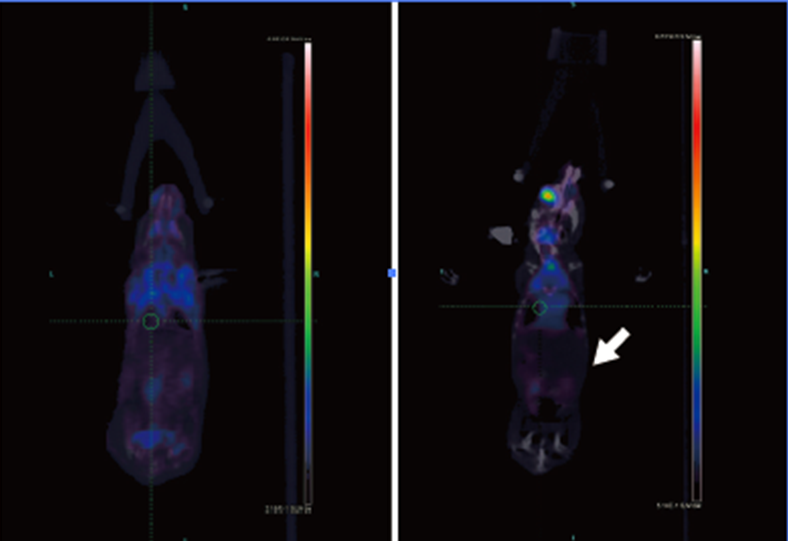

如图:左边为正常裸鼠肺部,摄取正常,右边白Micro-PET手段,可以活体筛选原位癌模型,并色箭头处为原位肺癌,肺部摄取增加。通过进行相关药效评价。